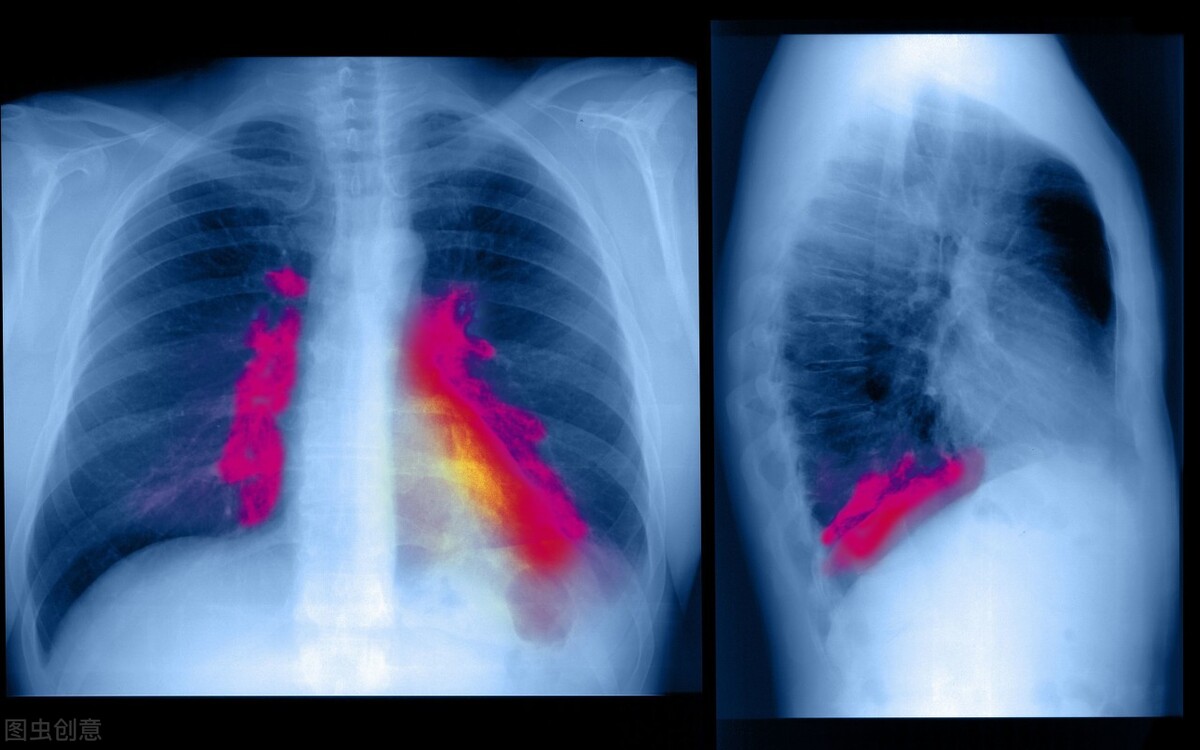

“肺结节”本身不是一种病,只是影像学上的一种概念,即影像学上直径大于或等于3厘米的类圆形或不规则病灶,即可单发也可多发,边界清晰也可不清晰。在通俗点来说就是肺里长了个东西,这个东西直径小于3厘米我们就称之为结节;小于1厘米我们称之为小结节;而直径小于5毫米的话就是微小结节了,所以总结来说肺结节就是一种肉芽类疾病。